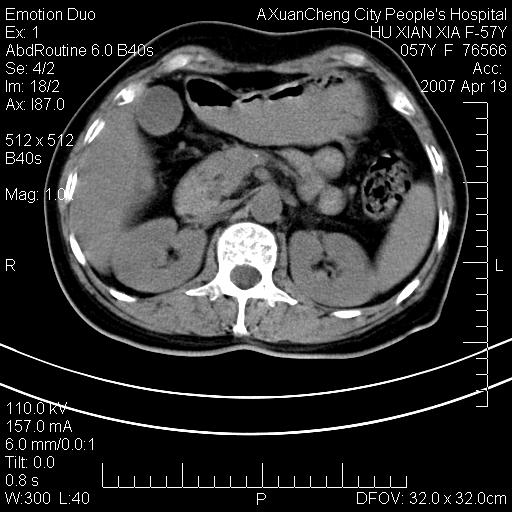

标题: CT7778:[原创]F,57Y腹痛待查,胸片提示肺部占位,应当很典型 [打印本页]

标题: CT7778:[原创]F,57Y腹痛待查,胸片提示肺部占位,应当很典型

胸片提示肺部占位

降结肠有无问题?双侧肾上腺占位

左侧肾上腺转移。

双侧肾上腺结节样肿块,结合肺部肿块,考虑肺癌肾上腺转移。

左侧肾上腺占位,建议结合病史,增强观察!

双侧肾上腺及腹膜后淋巴结增大,结合胸片提示肺部占位,考虑肺癌双侧肾上腺及腹膜后淋巴结转移.